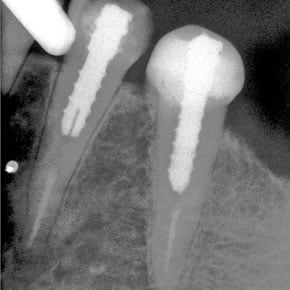

Superior Radiopacity

In an independent university study, The Biolight® DUAL material against exhibited superior radiopacity to all other fiber posts tested:

Radiopacity of fiber posts

| Biolight® DUAL: | 205.90 |

| FRC Postec® Plus: | 106.67 |

| RelyX™ Fiber Post: | 88.04 |

| ParaPost® Taper Lux: | 64.67 |

® or ™: Registered trademarks or trademarks of their respective manufacturer.